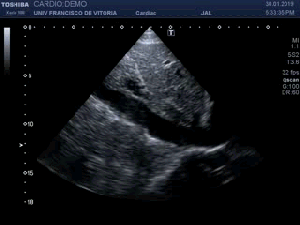

143. Ecocardiografía.Plano Apical 5 Cámaras.